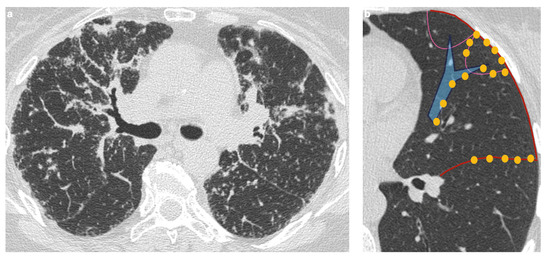

The Role of High-Resolution Lung Computed Tomography to Distinguish Between Fibrosing Hypersensitivity Pneumonitis and Usual Interstitial Pneumonia

Background: Hypersensitivity pneumonitis (HP) is an interstitial lung disease (ILD) caused by repeated exposure to inhaled antigens in susceptible subjects. High-resolution computed tomography (HRCT) of the lungs is the leading diagnostic method for ILDs, but in some cases HRCT findings are not sufficient to distinguish HP and other ILDs, particularly, fibrotic HP (fHP) and usual interstitial pneumonia (UIP). Objective: The aim of this study was to develop HRCT criteria to diagnose fHP in patients with a UIP-like pattern. Methods: In this retrospective study, we analyzed HRCT scans of patients with fHP and a UIP-like pattern who underwent lung biopsy, and patients with idiopathic pulmonary fibrosis (IPF) and a UIP pattern in HRCT. Results: We included 51 patients with confirmed fHP and 24 patients with IPF/UIP in the analysis. IPF/UIP patients were older, were prevalently males, and did not have any systemic autoimmune diseases or risk factors for other ILDs. fHP patients were younger, with an equal number of males and females, and were more likely to be exposed to environmental antigens. HRCT abnormalities in the fHP group predominated in the lower lung areas or were diffuse in axial scans, whereas IPF/UIP patients mostly demonstrated a diffuse craniocaudal distribution and subpleural axial predominance. Centrilobular nodules and mosaic attenuation were present significantly more often in the fHP group; honeycombing, traction bronchiectasis, and emphysema prevailed in IPF/UIP patients. In the logistic regression analysis, patients with fHP and IPF/UIP differed in the presence of centrilobular nodules, honeycombing, and in both craniocaudal and axial distributions of HRCT abnormalities. In the ROC analysis, the combination of centrilobular nodules, honeycombing, and diffuse axial and craniocaudal distributions can predict the diagnosis of fHP (AUC, 0.953 ± 0.022; 95%CI, 0.910–0.995; p < 0.001). Mosaic attenuation and reticulation did not change the probability of fHP. Conclusions: The most significant HRCT features of fHP compared to the UIP pattern were centrilobular nodules, honeycombing, and a diffuse axial and craniocaudal distribution of abnormal findings. Reticulation, mosaic attenuation, and GGO do not increase the probability of fHP. Full article

Figure 1